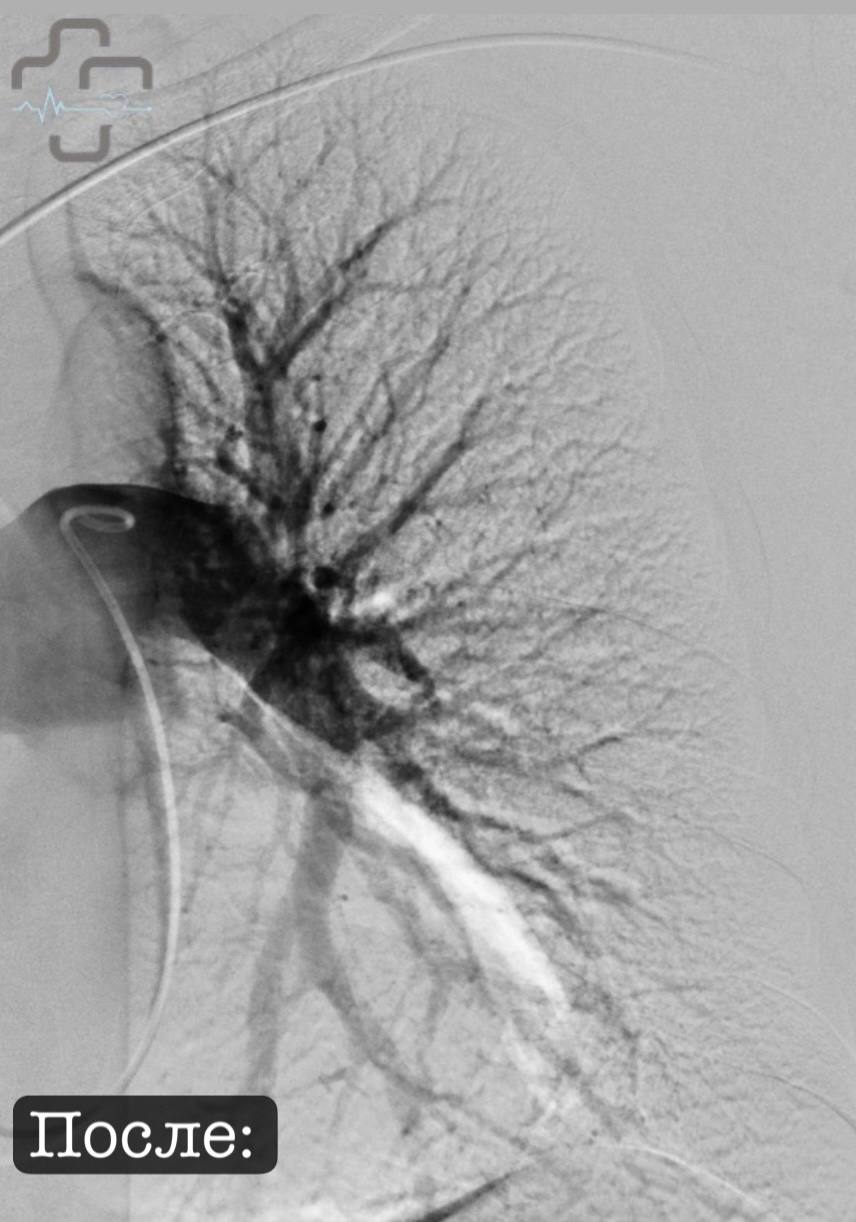

Пациентка из Оренбурга была переведена в Орск, где врачи применили ультразвуковой транскатетерный тромболизис — метод, который в России начали использовать только в 2024 году.

В отличие от обычного лечения, когда лекарство разжижают кровь во всем организме, новая методика работает точечно. Катетер вводят через бедренную вену прямо к тромбу, ультразвук помогает разрушить его и равномерно распределяет лекарство.

Тромбы растворились, легочные артерии свободны. Пациентка переведена из реанимации в палату, рассказали в горбольнице.